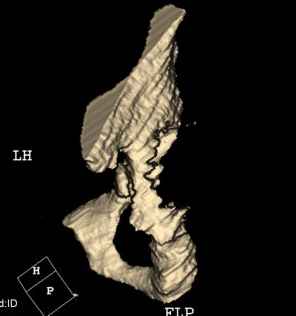

Мужчина, 45 лет. 6 мес. назад перенес тотальное эндопротезирование правого тазобедренного сустава по поводу ложного сустава шейки бедра.

Характер реконструкции вертлужной впадины не известен. Через 3 мес. после операции отметил щелчки и хруст при движениях в области эндопротеза. В анамнезе туберкулез легких. Сейчас, по заключению фтизиатра, в легких активного процесса нет. Местного воспаления нет.Предполагается нестабильность чашки в связи с бактериальным воспалением. Планируется удаление чашки и цемента, пластика дна измельченными аутотрансплантами и гидроксилапатитной керамикой, затем кольцо Мюллер, цементная чашка.

Смущает и ножка - зона просветления вокруг мантии. Предложения по тактике?

прямо скажем, очень загадочная конструкция с проволокой и винтами. :) На основании чего Вы подозреваете септическую нестабильность? Каковы результаты анализов? Согласен с доктором - нужно сделать пункцию. Есть ли снимки до и сразу после операции? Знаете ли Вы диаметр головки,какой будет внутренний диаметр Вашей чашки? Известно ли, чей протез? Может есть смысл найти автора работы и узнать о подробностях установки протеза?